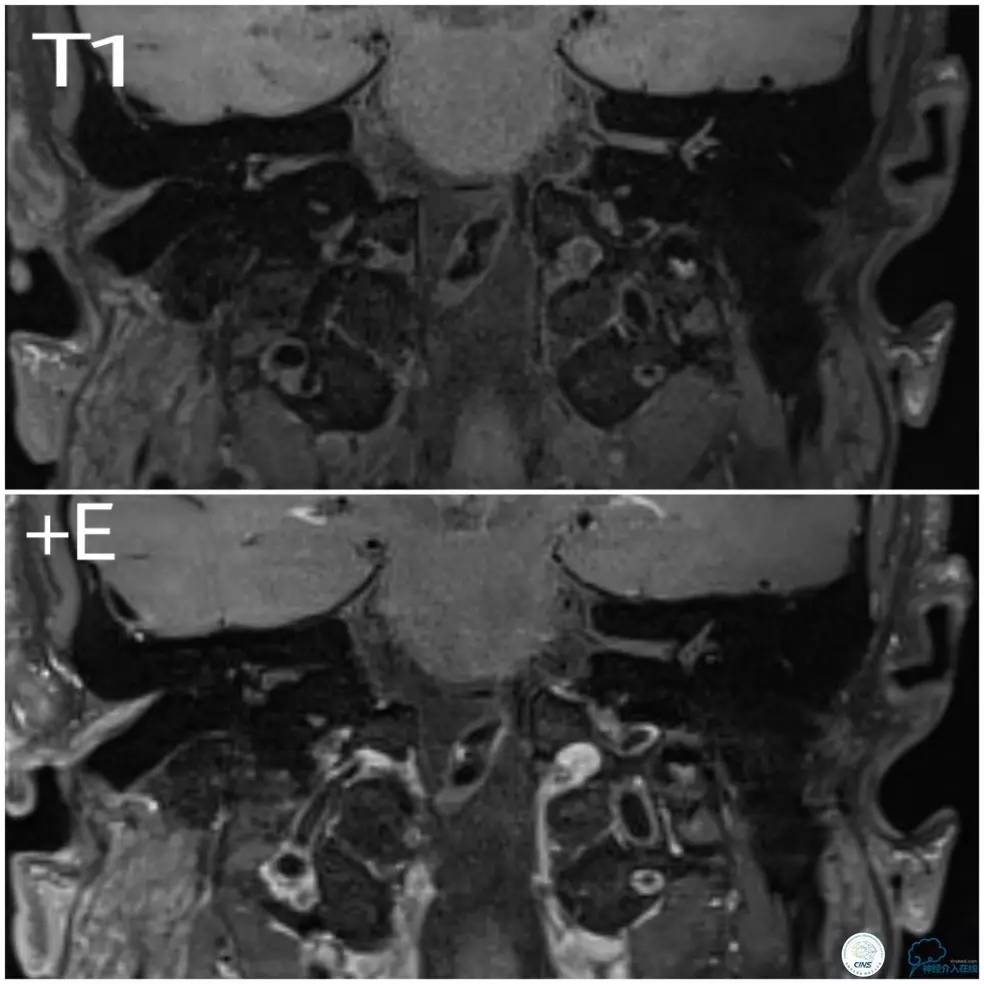

入院后查高分辨核磁:基底动脉局部可见偏心性狭窄,局部可见条状斑块,壁不均匀增厚,管腔内信号增高,注药后可见轻度强化,狭窄远端局部管腔扩张(图3)。右椎V4段略增粗,局部管壁不光滑,可见强化(图4)。左椎动脉显示不清。

图3

图4